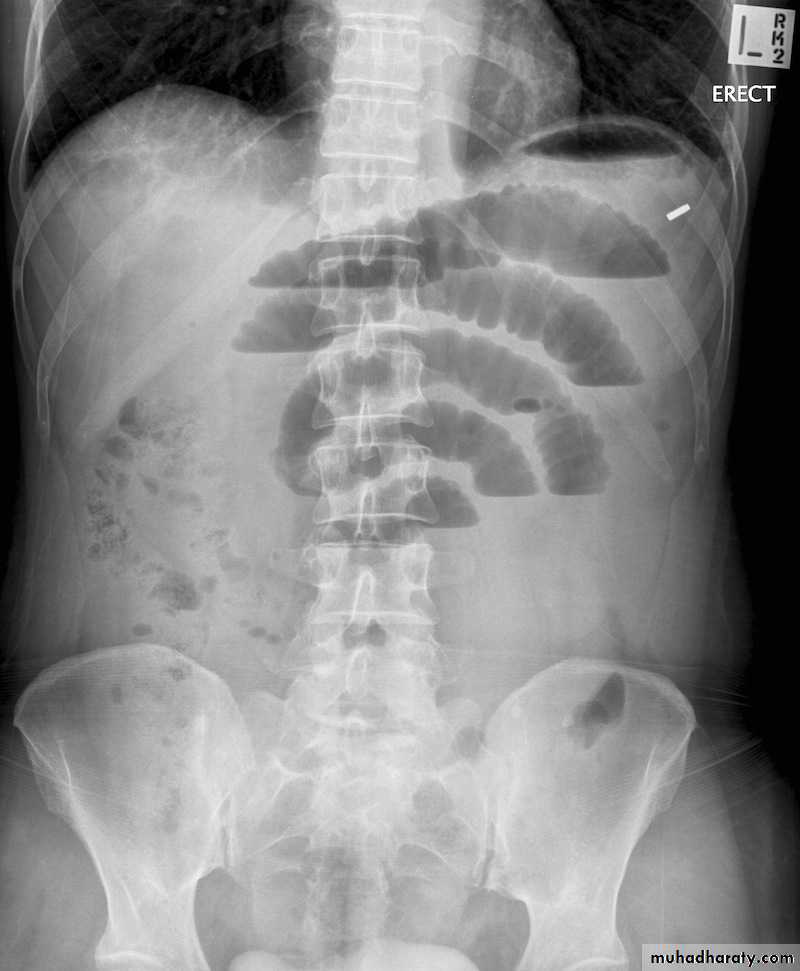

- upright films: dilated small bowel loops (>3 cm in diameter), air-fluid levels, and a paucity of air in the colon.

Small bowel obstruction

-The dilated bowel loops centrally located and lie transversely.-No/minimal gas is seen in the colon.

-valvulae conniventes,which completely pass across the width of the bowel

-ladder pattern

Multiple air fluid level, small and centrally located.

-Dilated loops of bowel

-periphery located.

-Larger bowel diameter

-Huastration (incomplete line)

-longer length airfuid level , less in number

Large bowel obstruction